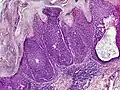

Microscopic histopathological examinations of the tumor tissues of all poroma variants stained with hematoxylin and eosin dyes reveal: a) basophilic "poroid cells" (i.e. small, cuboid-shaped cells with oval nuclei which resemble cells in the peripheral layer of the distal portion of eccrine sweat gland ducts[20]) that may form cords and broad columns extending downward from the epidermis; b) larger cuticular cells (i.e. squamous epithelial-like eosinophilic cells that resemble the luminal cells lining eccrine sweat gland ducts[20]); and in some cases c) clear cells (i.e. cells with small nuclei surrounded by pale cytoplasm).[3] Poroma tumor tissues may appear highly vascularized and/or have areas of necrosis, i.e. dead or dying cells. Hidroacanthoma simplex variants are mainly composed of poroid cells, few cuticular cells, and no clear cells and are confined to the epidermis; dermal ductal variants are mostly confined to the superficial dermis and are composed of small solid and cystic nodular aggregates of poroid, cuticular, and clear cells; poroid hidradenoma variants have large aggregates of solid and cystic components and extend deeper into the dermis or even subcutis; and eccrine poroma variants are composed of all three cell types but are primarily located in the epidermis and superficial dermis. Poromas may have 2 or more of these variants in the same tumor tissue and the variants typically have histopathology findings that are not clearly distinguishable from each other.[3]